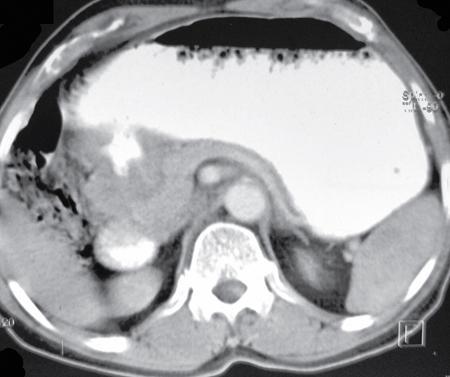

A 60-year-old male with history of chronic alcohol consumption and chronic weight loss and pain epigastrium presented to Radiology for USG. A finding on USG called for a barium meal and follow-through for academic purpose.

Barium meal and follow-through spot image revealed widening of C loop of duodenum along with extrinsic compression on the antrum posteroinferiorly giving rise to classical ‘antrum pad’ sign. There was, however, no obvious mucosal irregularity seen. There is evidence of contrast hold-up.

Analysis and interpretation

The image showcases two classical signs in GI radiology which are the ‘widening of C loop of duodenum’ and the ‘antral pad sign’. Both the signs are typically described in masses of head of pancreas. A comment on the mucosal lining (regular/irregular) may give a pointer towards the mass being malignant. However, this is a nonspecific sign giving indication of a mass effect and has a variety of differentials. The final diagnosis is reached with the help of cross-sectional imaging and/or endoscopy/biopsy. CECT abdomen in this case confirmed it to be a case of carcinoma pancreas (Fig. 7.4.6.1).

Image

Fig. 7.4.6.1 CECT showing a mass in the head of pancreas.

Pseudocyst of pancreas

• a) Two classical signs described above.

• b) Smooth indentation and smooth mucosa.

• c) USG/CT will show the cystic nature.

Fig. 7.4.6.3 CECT abdomen showing a large pseudocyst.